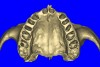

Periapical radiographs were taken to help determine the mesial-distal inclinations of the adjacent tooth roots (Figure 1). The radiographs revealed a serious issue, convergent roots for the right canine and right central, which eliminated that area as a potential implant-receptor site. The space between the left central and canine teeth was minimal, although the roots were relatively parallel. Clinical examination (manual palpation of the root eminences superiorly to the vestibule on the right side) confirmed the root convergence (Figure 2A). The flat, wide zone of the keratinized tissue and lack of interdental papilla was evident for the missing right lateral incisor. There was a marked difference in clinical appearance for the left lateral, which could impact the eventual plan of treatment (Figure 2B). Other significant clinical findings included bilateral facial bone concavities, which existed as a result of the congenitally missing tooth roots. As a diagnostic cue to the underlying bone topography, it is important to follow the demarcation between attached and unattached gingival tissue, and note the crestal width of the available keratinized tissue (Figure 2C).

Figure 2a  Pretreatment buccal views showed (A) root convergence, (B) a difference in clinical appearance of the left lateral, and (C) significant crestal width of keratinized tissue.

Figure 2a